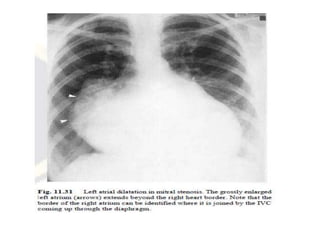

• The chest radiograph : selective left atrial

enlargement, which can vary from trivial to

gross.

• The right-sided cardiac chambers will often be

considerably enlarged ,the presence of a

'double right heart border.

• A very large left atrium, aneurysmal if it

reaches to within 2.5 cm of the thoracic wall,